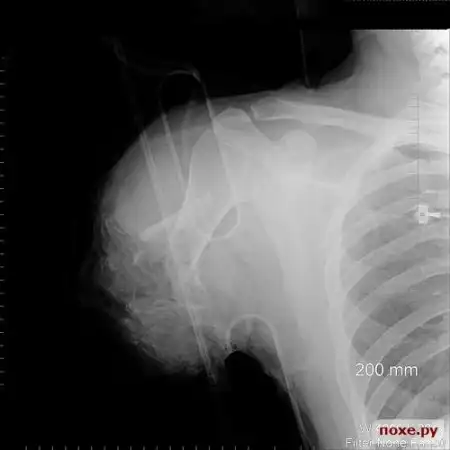

Промышленная травма. Ампутация руки.